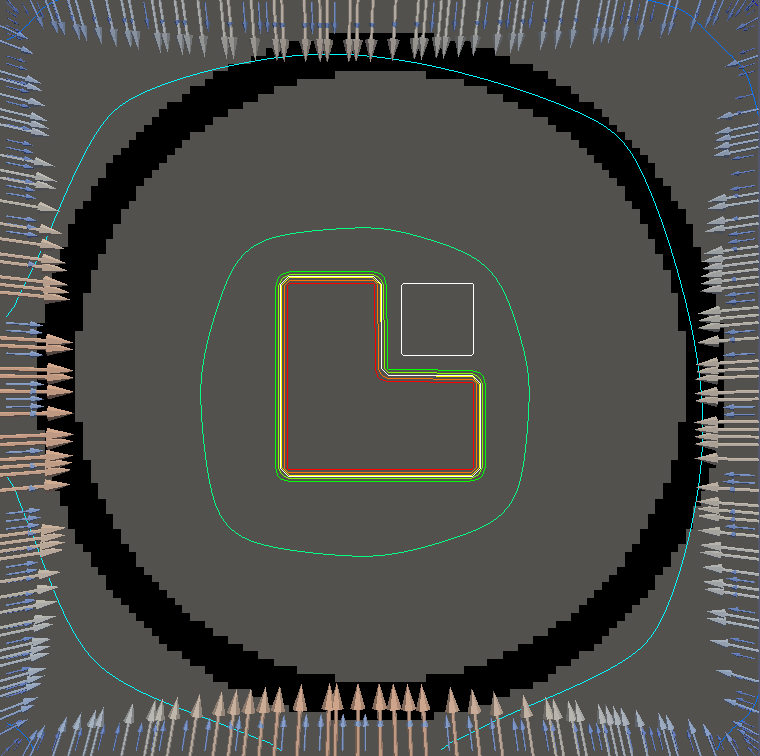

For testing, we use three tumor/risk region regions similar to those in [13]. Specifically, we define the regions in Table 3 and are shown in Figure 1; the void region is shown in black and the tumor and risk regions are traced in white. In the basic target case, seen in Figure 1(a), the tumor region is a box, as is the risk region. The second, intermediate target case, seen in Figure 1(b), involves an L-shaped tumor around a box-shaped risk region. Finally, the complex target case in Figure 1(c) involves a C-shaped tumor around a risk region.

Figure 2 shows the optimal boundary source term for both and The vectors shown on the boundary are the time-integrated values of normalized and then scaled by In Figures 2(a), 2(c), and 2(e) (corresponding to ), the isolines are spaced at intervals of the maximum of the desired dose (here, 5). In the intermediate and tracking cases, we see that relatively low dose levels are attained, primarily due to the high penalty to any dose deposited in the risk region. In Figures 2(b), 2(d), and 2(f)(corresponding to ), the isolines are spaced at intervals of of cells killed. Here a high proportion of the tumor cells are killed (in each case ) while in the Intermediate and Basic cases, the tumor has at least survival; in the Complex case, the risk region has survival.